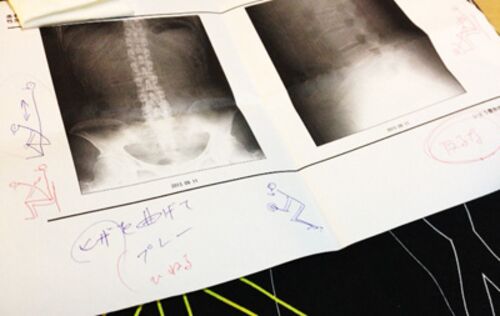

札幌へ旅立つ前々日から、とつぜんかがめず、すぐ立てずという腰痛がでてきて、鍼灸の先生にテーピングで応急処置してもらって旅だったのですが、腰をかばうあまり、背中のこりが半端なく張ってて、毎晩ホテルのマッサージにかかるということをしておりまし…